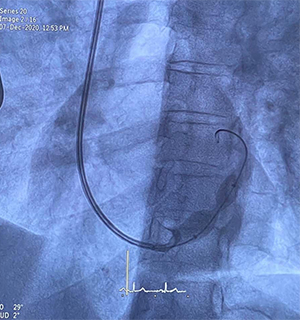

Η πρώτη επέμβαση στην Ελλάδα, εμφύτευσης της συσκευής «Reducer» στον στεφανιαίο κόλπο της καρδιάς για την αντιμετώπιση της ανθεκτικής στηθάγχης, διενεργήθηκε με επιτυχία στο νοσοκομείο Ερρίκος Ντυνάν από τον επεμβατικό καρδιολόγο Γιώργο Τζάνη και τη συνδρομή όλης της ομάδας της κλινικής επεμβατικής καρδιολογίας.

Πρόκειται για μια νέα πρωτοποριακή επέμβαση για την αντιμετώπιση της ανθεκτικής στηθάγχης και της ισχαιμίας μυοκαρδίου σε ασθενείς με εκτεταμένη στεφανιαία νόσο. Η συσκευή μοιάζει με ένα “stent” σχήματος κλεψύδρας, που τοποθετείται εντός του στεφανιαίου κόλπου ώστε να προκαλέσει στένωση του αυλού του, προκαλώντας ανακατανομή της αιμάτωσης του μυοκαρδίου.

Η συσκευή Reducer μοιάζει με "stent" σχήματος κλεψύδρας και τοποθετείται διακαθετηριακά από την έσω σφαγίτιδα στον στεφανιαίο κόλπο της καρδιάς ενώ διενεργείται με τοπική αναισθησία. Ο ασθενής επανέρχεται πλήρως στις δραστηριότητές του την επόμενη ημέρα, ενώ η βελτίωση των συμπτωμάτων αναμένεται σε διάστημα 2-3 μηνών.